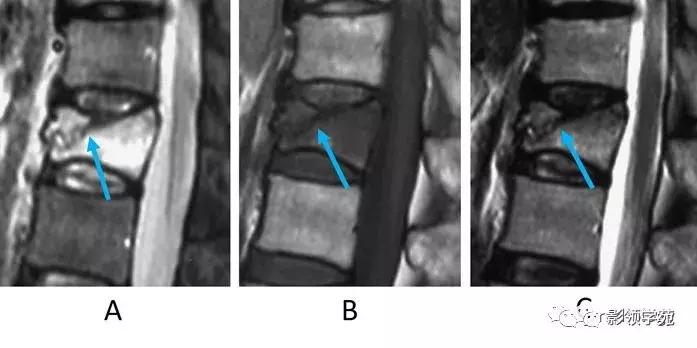

- FS-T2WI或STIR的信号改变有助于我们区分急性或陈旧性骨折。

- 受伤后约一个月,FS-T2WI或STIR(图2-A)示椎体内高信号是反映了骨小梁坏死和反应性骨生成。

- 一个月或更长时间后,FS-T2WI或STIR中的高强度信号区域在椎体减少并由脂肪信号代替(:T1WI和T2WI高信号,FS-T2WI或STIR低信号)。

- 平行于T1WI和T2WI终板的低信号强度带提示压缩的小梁(图2-B,C箭头)。

图2:急性椎体骨折(楔形压缩骨折)。A:STIR矢状面图像,B:T1WI矢状面图像,C:T2WI矢状面图像。女,70岁。下胸椎椎体呈楔形改变。STIR(A)骨髓信号强度高,T1WI低(B),T2WI混合信号强度(C)。每个序列在椎体中显示低信号强度线,反映压缩的小梁(A,B,C箭头)。